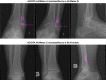

Purpose: Convolutional neural networks (CNNs) are increasingly being developed for automated fracture detection in orthopaedic trauma surgery. Studies to date, however, are limited to providing classification based on the entire image-and only produce heatmaps for approximate fracture localization instead of delineating exact fracture morphology. Therefore, we aimed to answer (1) what is the performance of a CNN that detects, classifies, localizes, and segments an ankle fracture, and (2) would this be externally valid?

Methods: The training set included 326 isolated fibula fractures and 423 non-fracture radiographs. The Detectron2 implementation of the Mask R-CNN was trained with labelled and annotated radiographs. The internal validation (or 'test set') and external validation sets consisted of 300 and 334 radiographs, respectively. Consensus agreement between three experienced fellowship-trained trauma surgeons was defined as the ground truth label. Diagnostic accuracy and area under the receiver operator characteristic curve (AUC) were used to assess classification performance. The Intersection over Union (IoU) was used to quantify accuracy of the segmentation predictions by the CNN, where a value of 0.5 is generally considered an adequate segmentation.

Results: The final CNN was able to classify fibula fractures according to four classes (Danis-Weber A, B, C and No Fracture) with AUC values ranging from 0.93 to 0.99. Diagnostic accuracy was 89% on the test set with average sensitivity of 89% and specificity of 96%. External validity was 89-90% accurate on a set of radiographs from a different hospital. Accuracies/AUCs observed were 100/0.99 for the 'No Fracture' class, 92/0.99 for 'Weber B', 88/0.93 for 'Weber C', and 76/0.97 for 'Weber A'. For the fracture bounding box prediction by the CNN, a mean IoU of 0.65 (SD ± 0.16) was observed. The fracture segmentation predictions by the CNN resulted in a mean IoU of 0.47 (SD ± 0.17).